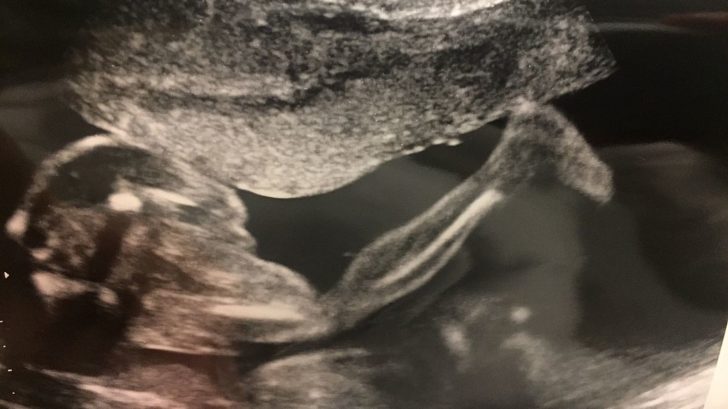

Na velký ultrazvuk se nastávající maminky většinou těší nejen proto, že se dozví, jestli je jejich miminko v pořádku, jak je velké, ale hlavně, jaké pohlaví čekají. Já jsem byla na ultrazvuku přesně na Valentýna, těšila jsem se, až malého (malou) uvidím. A i když pocitově vím, že je vše v pořádku, ulevilo se mi, že tomu tak skutečně je. Mimčo prospívá, měří a váží zhruba tolik, kolik má. Sedí počet prstíků a srdíčko krásně bije. Nic mu nechybí. „Mám se podívat na pohlaví?“, zeptal se mě pan doktor. „My se necháme překvapit,“ ztěžka jsem vykoktala a dodala: „Myslíte, že kdybyste se podíval, tak to poznám?“ Odpověď jsem stejně znala, jasně, že asi jo, o tom, že je Sebík kluk, nebylo pochyb, to by z toho záběru poznalo snad i malé dítě!

Do patřičných míst pan doktor teda nezajížděl, ale stejně mi pak řekl, že když kolem brousil, troufá si říct, že pohlaví zná. A asi se mu líbilo mě škádlit, protože když najel na nohu miminka, říkal, že takhle krásnou atletickou nohu dlouho neviděl! „Co myslíte, je to noha běžce nebo baletky?“ No měla jsem co dělat, abych si to nenechala říct, ale vydržela jsem! Slib je slib. Schválně, posuďte sami, bude to kluk nebo holka?